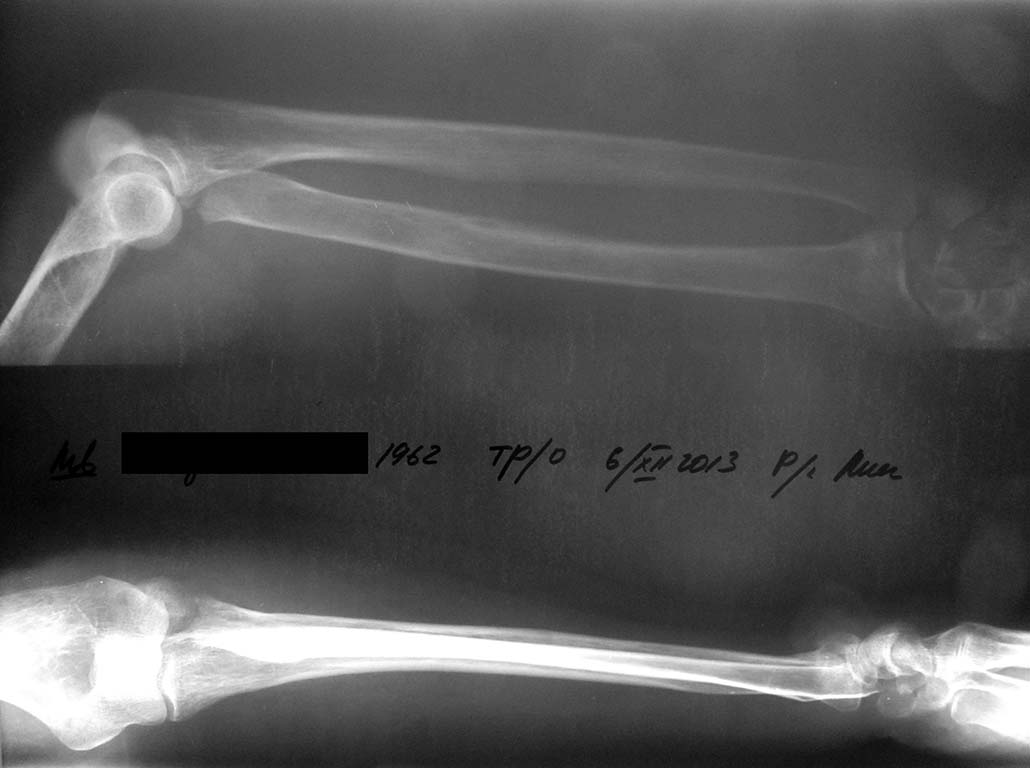

Здравствуйте, всем доброй ночи. Поступила женщина 50 лет. Перелом шейки лучевой кости слева. Чрезмыщелковый перелом плеча слева. Перелом лучевой кости слева со смещением+ шиловидный отросток локтевой кости.

Интересно, что все как один участники дискуссии говорят только об остеосинтезе или протезировании головки луча и операции на дистальном отделе. Неужели эти операции так прочно вошли в повседневную практику? Фрагмент головки маленький, значительное смещение. Вероятность несращения в случае остеосинтеза высокая. Почему просто не удалить головку и не приступить к ранней разработке движений? А смещение дистального луча вовсе ерундовое. Опять не могу понять, сейчас принято синтезировать подобные переломы без попытки ручной репозиции? Это же все травматологи только и будут с утра до вечера делать остеосинтезы лучей в типичном месте. И еще не очень понял насчет ретроградного остеосинтеза головки луча двумя тэнами. Их же вводят через дистальный конец лучевой кости? То есть ими же будет синтезирован и дистальный перелом?

Завтра операция. Остановились на минимальной ивазии. Резекция головки, закрытая репозиция луча. Ну а если расшатается чрезмыщелковый перелом, тогда будет интересно.

я бы протестировал сустав в условиях анестезии, если блока нет - функциональное лечение. А на счет луча - снимки непонятные, во всяком случае - лечить как луч